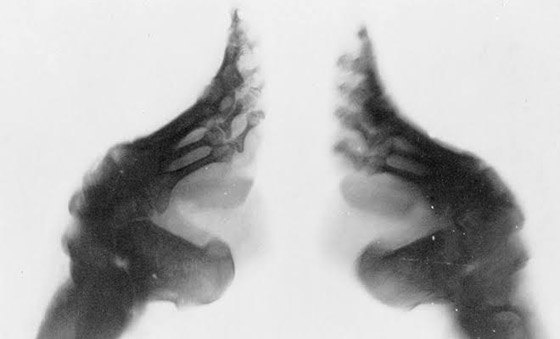

سُميت الأقدام الصغيرة في الصين بـ قدم اللوتس لشكلها القريب من زهرة اللوتس ، وكانت النساء ذات القدم الكبيرة محلاً للسخرية والإذلال ويُنظر إليهن بأنهن من عامة النساء العاملات في الحقول وأنه لا يمكنهن تحمل رفاهية قدم اللوتس، ولم تكن عملية طي الأقدام في الصين بسيطة بل كانت تُمثل علماً مهماً في القرون القديمة وكانت تبدأ بالاستعداد النفسي لتحمل الآلام عن طريق إقناع الفتيات بأن طي الأقدام سيجعلهن أكثر جمالاً وستفتح أمامهن آفاقاً جديدة للزواج. بعدها تبدأ عملية الطي بعد غسل القدمين جيداً وقص الأظافر وطي الأصابع ما عدا الإصبع الكبير من ثم تضميد الأصابع ثم الكعب ومحاولة تقريبهما مع بعض قد الإمكان وإحكام الضمادات جيداً على تلك الوضعية وبعدها إدخال القدمين في حذاءٍ ضيق جداً ويتم تغيير الضمادات يومياً لضغط القدم بشدة أكثر في كل مرة وهي عملية تسبب ألماً كبيراً للأطفال لأنها تُعيق حركاتهن لعدة أيام وشهور. وإضافةً لسلبيات طي القدمين فإن رائحتها تكون صعبة جداً خلال فصل الصيف بسبب الدم اء والقيح كما أنها تتجمد في فصل الشتاء بسبب نقص تدفق الأكسجين في الدم وبعض النظر عن كل ذلك فهي عملية مؤلمة للغاية تغير في معالم جسم المرأة الصينية كونها تضع الضغط كله على الفخذين والأرداف مما يؤدي لإنتفاخهما وإصابة الساقين بالإعوجاج فضلاً عن المعاناة الجسدية التي تصاحب هؤلاء النساء مدى الحياة.